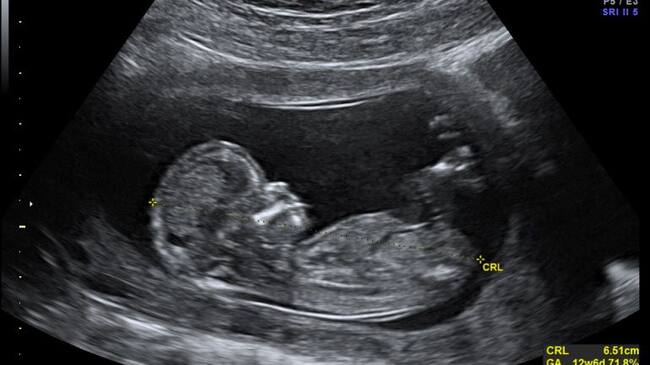

Ecografía de un bebé / Cadena SER

En total, según consta en los informes, se realizaron cinco ecografías calificadas todas ellas como "normales" y sin detección de anomalía alguna o hallazgo patológico, ni la concurrencia de circunstancias particulares de la embarazada que pudieran dificultar la visión del feto.

En concreto, en la ecografía 20 se apreciaba "complitud" de las extremidades superiores e inferiores del feto, sin anomalía o malformación algunas, lo cual, aún tratándose de una técnica no infalible y de limitada capacidad diagnóstica pese a su alta detectabilidad pero con variable sensibilidad, "pone de manifiesto el error de diagnóstico en que se incurrió reiterado en todas las ecografías".